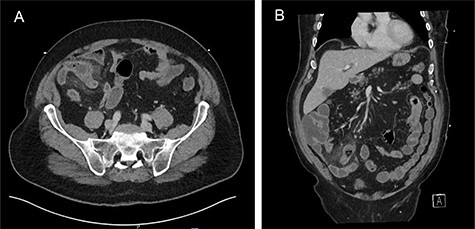

On examination, he had normal observations, his abdomen was distended, bowel sounds were present with tenderness and localized guarding of RIF and suprapubic area. His blood tests showed an elevated white cell count and C-reactive protein, 17.2 × 10^9/L and 186 mg/L, respectively. He subsequently had a computer tomography (CT) (Fig. 1), which showed a blind-ending tubular structure in the RIF arising off the ileum that measured 5 cm in length and contained fecalized material within the tip associated with extensive adjacent stranding of the mesentery consistent with acute Meckel’s diverticulitis. The appendix was normal.

(A) Axial and (B) coronal views: acute Meckel’s diverticulitis in RIF associated with extensive adjacent mesenteric stranding.